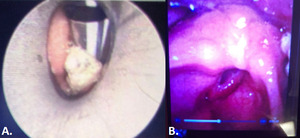

On the second day of admission, she underwent tracheostomy and direct laryngoscopy that revealed an obstructive well-circumscribed glottic mass with supraglottic edema and a laryngeal mass (Figure 2). Glottic mass biopsy demonstrated acute inflammation, granulation tissue without tumor cells. Sedation was progressively weaned until the 6th day of admission when she became tachypneic, oliguric, and became febrile to 101.2 degrees F, prompting empiric coverage with antibiotics. Infectious workup with plain chest radiograph, urinalysis, and blood counts was non-revealing. Blood and sputum cultures taken during this time grew Group G Streptococcus, and the patient was started on intravenous ceftriaxone. She improved clinically over the next ten days. Bedside laryngoscopy done during tracheostomy tube exchange showed complete resolution of the previously identified glottic mass (Figure 2). The patient was subsequently decannulated and discharged home. Follow up two weeks after discharge demonstrated complete resolution of the previously described lesions with no residual scarring.